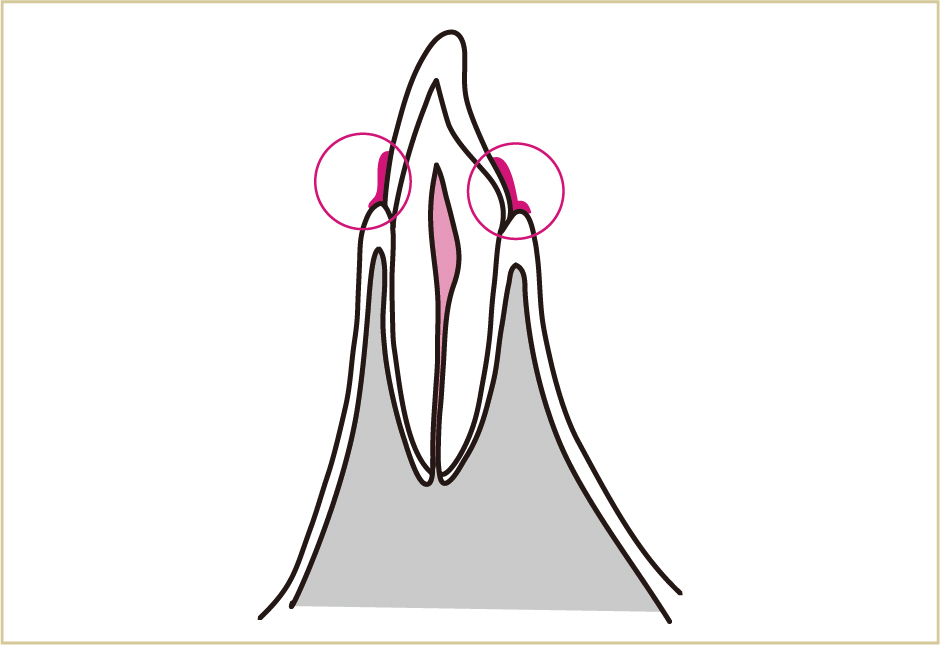

歯と歯肉の境目にプラーク(歯垢)がつき、そこから歯肉や骨にまで炎症が生じます。

さらに病状が進行すると、細菌による毒素は、歯肉だけでなく、歯を支える骨や歯根表面にまで悪影響を与える。その結果として、歯を支える骨が壊れていく。

上の図は歯を横から見た所です。歯と歯肉の境目を、毎日しっかりきれいにすることが、歯周病予防につながります。